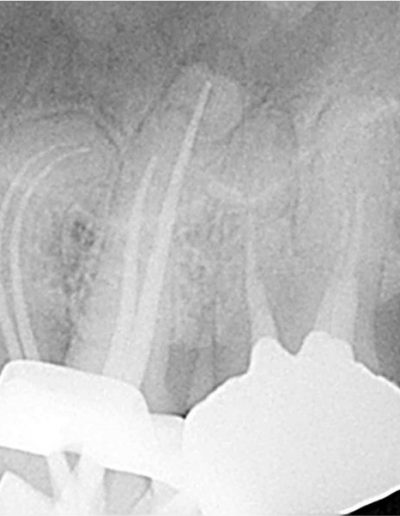

冠状の低侵襲アクセス。